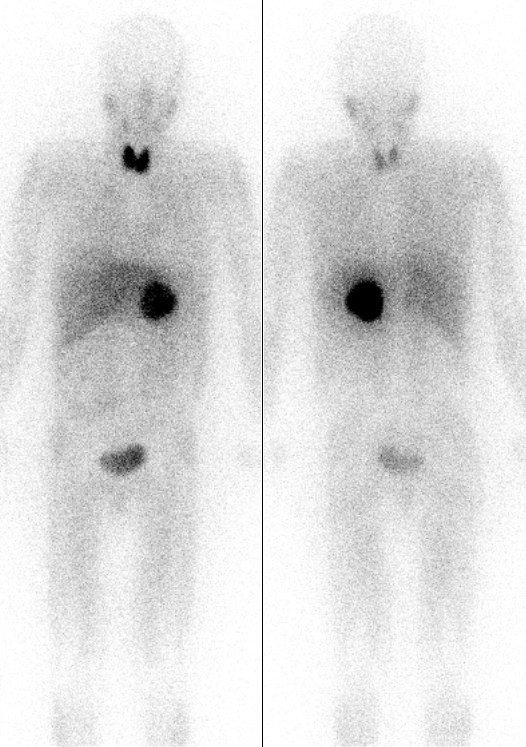

영상 검사로는 CT, MRI, 131I-MIBG 신티그래피, PET 등이 있다.[82] CT와 MRI는 종양의 위치, 크기, 주변 구조와의 관계를 파악하는 데 유용하다.[82] 131I-MIBG 신티그래피는 부신 외 원발 병변이나 전이 병변의 위치를 확인하는 데 사용된다.[88] MIBG는 노르에피네프린과 유사한 구조를 가져 종양 세포에 섭취되는 원리를 이용한다. PET 검사는 MIBG 섭취가 없는 경우에도 양성으로 나타날 수 있으며, 전이 병변 검색에 유용하다.[90] 특히, 68Ga-DOTA 유사체를 이용한 PET 검사는 소마토스타틴 수용체 영상 기법으로, 다른 기능적 영상 검사보다 우수한 성능을 보인다.[94][95][97]